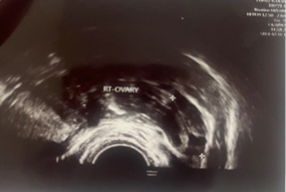

A 23-year-old asymptomatic female patient. During a routine gynecological examination, pelvic ultrasound identified a nonspecific tumor-like mass of solid consistency (Figures 1-3). The patient is sexually active and nulliparous. She has no history of abnormal menstrual bleeding or pelvic pain. Pelvic ultrasonography demonstrated a nonspecific tumor-like mass. The lesion was located in the vesicouterine space, anterior to the uterus (which was in anteversion and anteflexion with length 6.5 cm.) and posterior to the urinary bladder. The mass measured approximately 10 cm and had a predominantly solid component, with multilaminar hypoechoic bands within its capsule (Figures 1 and 4). Both ovaries were visualized and appeared normal on transvaginal ultrasonography (Figures 2 and 3). The pouch of Douglas is free of fluid.

Figure 3: TV-Ultrasonography image of right ovar-normal view.